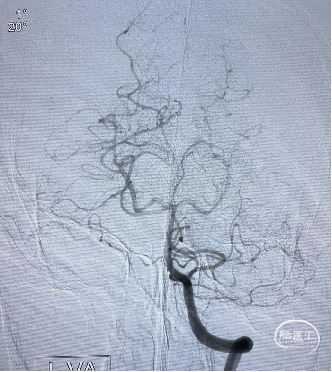

![]() 后循环造影

后循环造影